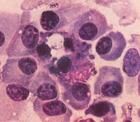

宮頸表面呈顆粒狀或有潰瘍形成、少數呈乳頭狀或結節狀、有明顯的接觸出血,病理切片可見結核結節、由於乾酪壞死組織、類上皮細胞、多核巨細胞組成,外層有多數淋巴細胞浸潤。宮頸組織病理檢查是診斷最可靠的依據。

宮頸表面呈顆粒狀或有潰瘍形成、少數呈乳頭狀或結節狀、有明顯的接觸出血,病理切片可見結核結節、由於乾酪壞死組織、類上皮細胞、多核巨細胞組成外層有多數淋巴細胞浸潤鶒。宮頸組織病理檢查是診斷最可靠的依據。

1.宮頸組織病理檢查若宮頸可疑結核,應做活組織檢查確診鶒在病理切片上找到典型結核結節,診斷即可成立但陰性結果並不能排除結核的可能。